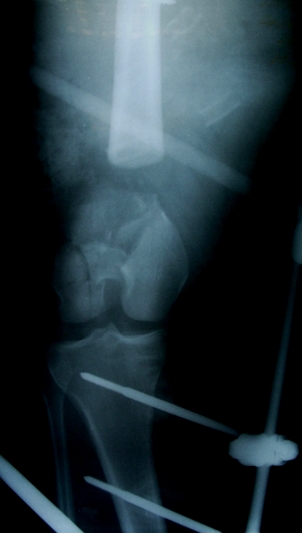

Больной 27 лет, мотоциклист. Поступил 23.04.10

ДЗ. О. перелом н.з левого бедра Gustillo 3b (c повредрение бедренной вены),

О.Правого бедра Gustillo 2, з. фрагментарный перелом левой голени.

При поступлении Hb 66 ISS 40, фиксация стержневыми аппратами, сосудистые

хирурги выполнили шов вены. Выполена резекция бедренной кости 9 см

Вопрос: что делать с левым бедром? Учитывая внутрисутавной характер

перелома, дефект бедра 9 см.